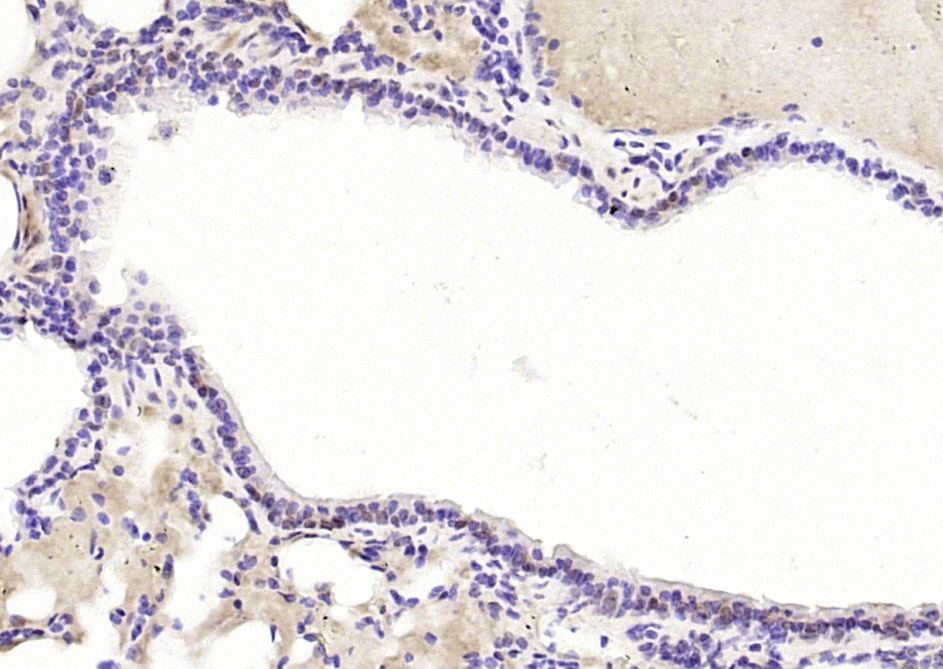

Paraformaldehyde-fixed, paraffin embedded (mouse lung); Antigen retrieval by boiling in sodium citrate buffer (pH6.0) for 15min; Block endogenous peroxidase by 3% hydrogen peroxide for 20 minutes; Blocking buffer (normal goat serum) at 37°C for 30min; Antibody incubation with (TRAF6BP) Polyclonal Antibody, Unconjugated (bs-13671R) at 1:200 overnight at 4°C, followed by operating according to SP Kit(Rabbit) (sp-0023) instructionsand DAB staining.